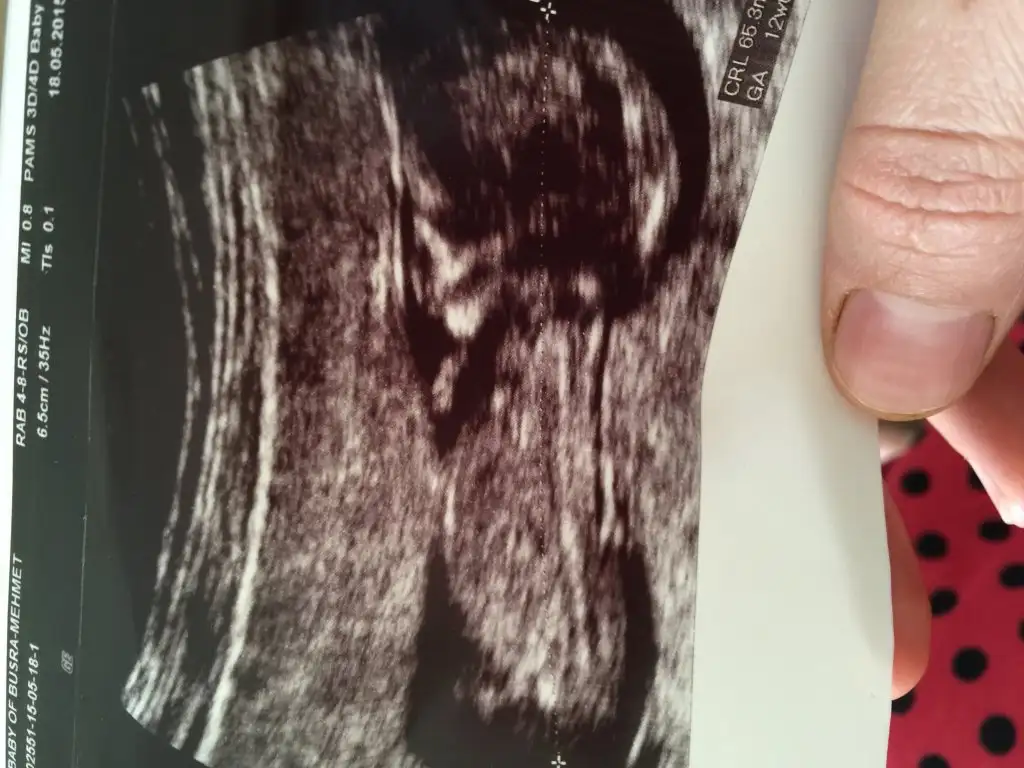

Rabbim hayırlısıni inş.gönlümüzün isteğiyle verir canım mariamelikem sanki seninki erkek mi yukarı bakan bi çıkıntı var gibi

Ya ben pek anlamıyorum canım neye göre söyledin çok merak ettim de :) doktor bize kesin kız dedi ama bana hiç öyle gelmiyor..

Canım kordonunun hemen altında bir çıkıntı daha var. Yukarı açılı duruyor. Bu erkek bebek nubudur. Eğer görüntüden kaynaklanan bir sıkıntı yoksa bence bu bebek erkek. Çünkü nubu o kadar Yukarıdan başlayıp, yukarı açılı olan ancak erkek bebek olabilir :) ayrıca neye göre kesin kız dedi ki?

Bilmiyorum ki hatta o kadar emindi ki %100 kız git herkese söyle dedi benim çevremdeki herkeste hiç kıza benzemiyor erkek bu diyorlar ben arkadaşımın ısrarı üzerine onun doktoruna gittim o böyle dedi 2 hafta sonra kendi doktoruma gideceğim bakalım o ne diyecek ayrıca cevap verdiğin için çok teşekkür ederim.